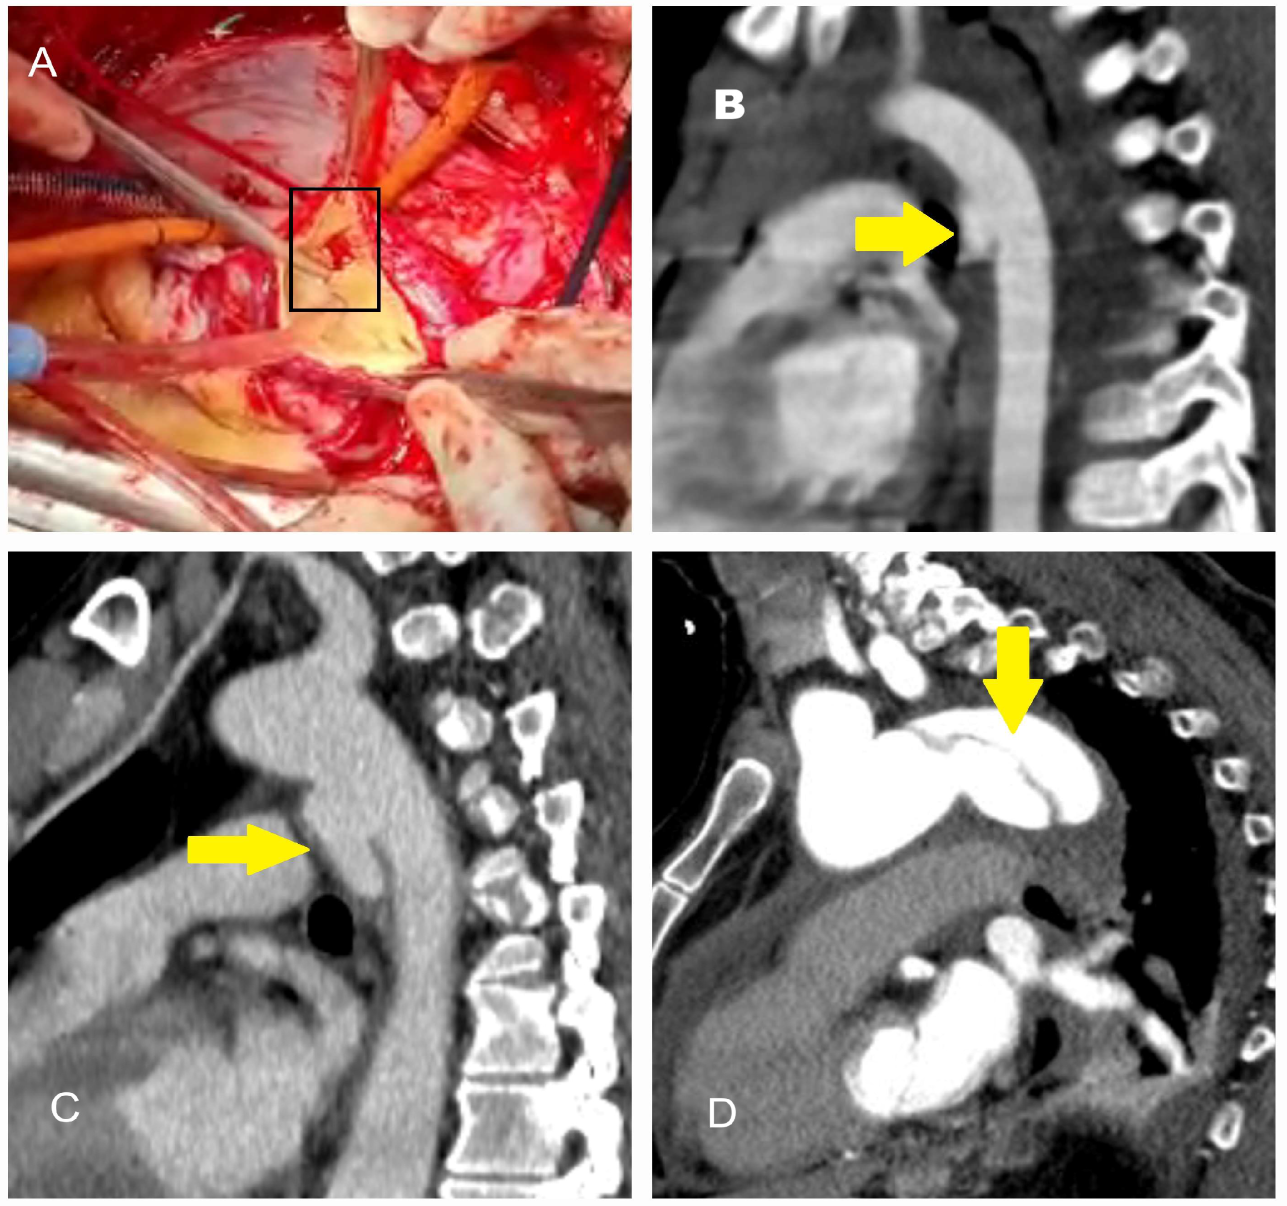

4.1. Dissection, Intramural Hematoma, and Penetrating Aortic Ulcer